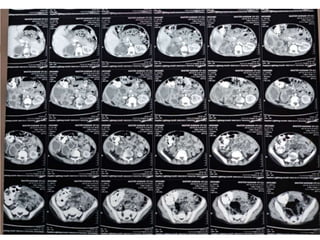

 CT-scan

Diagnosis  Based onsymptoms and urine analysis  Urine DR and CS  Urine sample (toilet trained and untoilet trained)  CBC (leukocytosis and neutrophilia suggest acute renal infection)  Increased ESR  Increased CRP  Ultrasound  CT-scan